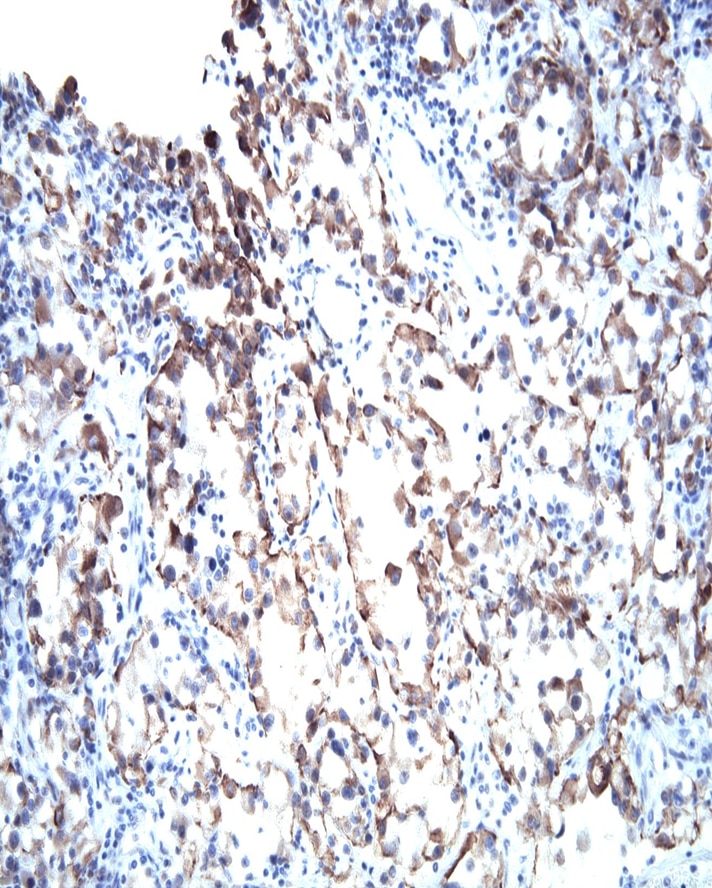

VHL Immunohistochemical staining on human renal cell carcinoma. Formalin fixed paraffin embedded human renal cell carcinoma was pretreated with BD Retrervagen A (Cat. No. 550524) and then stained with either Purified Mouse IgG1, κ isotype control (Clone MOPC-21; Left Panel) or Purified Mouse anti-VHL (Right Panel).

VHL Immunohistochemical staining on human renal cell carcinoma. Formalin fixed paraffin embedded human renal cell carcinoma was pretreated with BD Retrervagen A (Cat. No. 550524) and then stained with either Purified Mouse IgG1, κ isotype control (Clone MOPC-21; Left Panel) or Purified Mouse anti-VHL (Right Panel).

VHL Immunohistochemical staining on human renal cell carcinoma. Formalin fixed paraffin embedded human renal cell carcinoma was pretreated with BD Retrervagen A (Cat. No. 550524) and then stained with either Purified Mouse IgG1, κ isotype control (Clone MOPC-21; Left Panel) or Purified Mouse anti-VHL (Right Panel).

VHL Immunohistochemical staining on human renal cell carcinoma. Formalin fixed paraffin embedded human renal cell carcinoma was pretreated with BD Retrervagen A (Cat. No. 550524) and then stained with either Purified Mouse IgG1, κ isotype control (Clone MOPC-21; Left Panel) or Purified Mouse anti-VHL (Right Panel).

VHL Immunohistochemical staining on human renal cell carcinoma. Formalin fixed paraffin embedded human renal cell carcinoma was pretreated with BD Retrervagen A (Cat. No. 550524) and then stained with either Purified Mouse IgG1, κ isotype control (Clone MOPC-21; Left Panel) or Purified Mouse anti-VHL (Right Panel).

VHL Immunohistochemical staining on human renal cell carcinoma. Formalin fixed paraffin embedded human renal cell carcinoma was pretreated with BD Retrervagen A (Cat. No. 550524) and then stained with either Purified Mouse IgG1, κ isotype control (Clone MOPC-21; Left Panel) or Purified Mouse anti-VHL (Right Panel).

Immunohistochemistry: The Ig32 antibody is useful for immunohistochemical staining. Following Retrievagen A pretreatment, purified Ig32 antibody should be used at 2.5 µg/ml to 5 µg/ml and titrated for optimal indirect immunohistochemical staining. Tissues can be visualized via a three-step staining procedure in combination with Biotin Goat anti-Mouse Ig (Cat. No. 550337) secondary antibody and Streptravidin-HRP (Cat. No. 550946) together with the DAB Substrate Kit (Cat. No. 550880). More conveniently, the Anti-Mouse Ig HRP Detection Kit (Cat. No. 551011) that contains the biotinylated secondary antibody, antibody diluent, streptavidin-HRP and DAB substrate can be used for staining. For IHC staining on paraffin sections, please refer to http://www.bdbiosciences.com/documents/Immuno_Prep_Stain_Paraffin.pdf